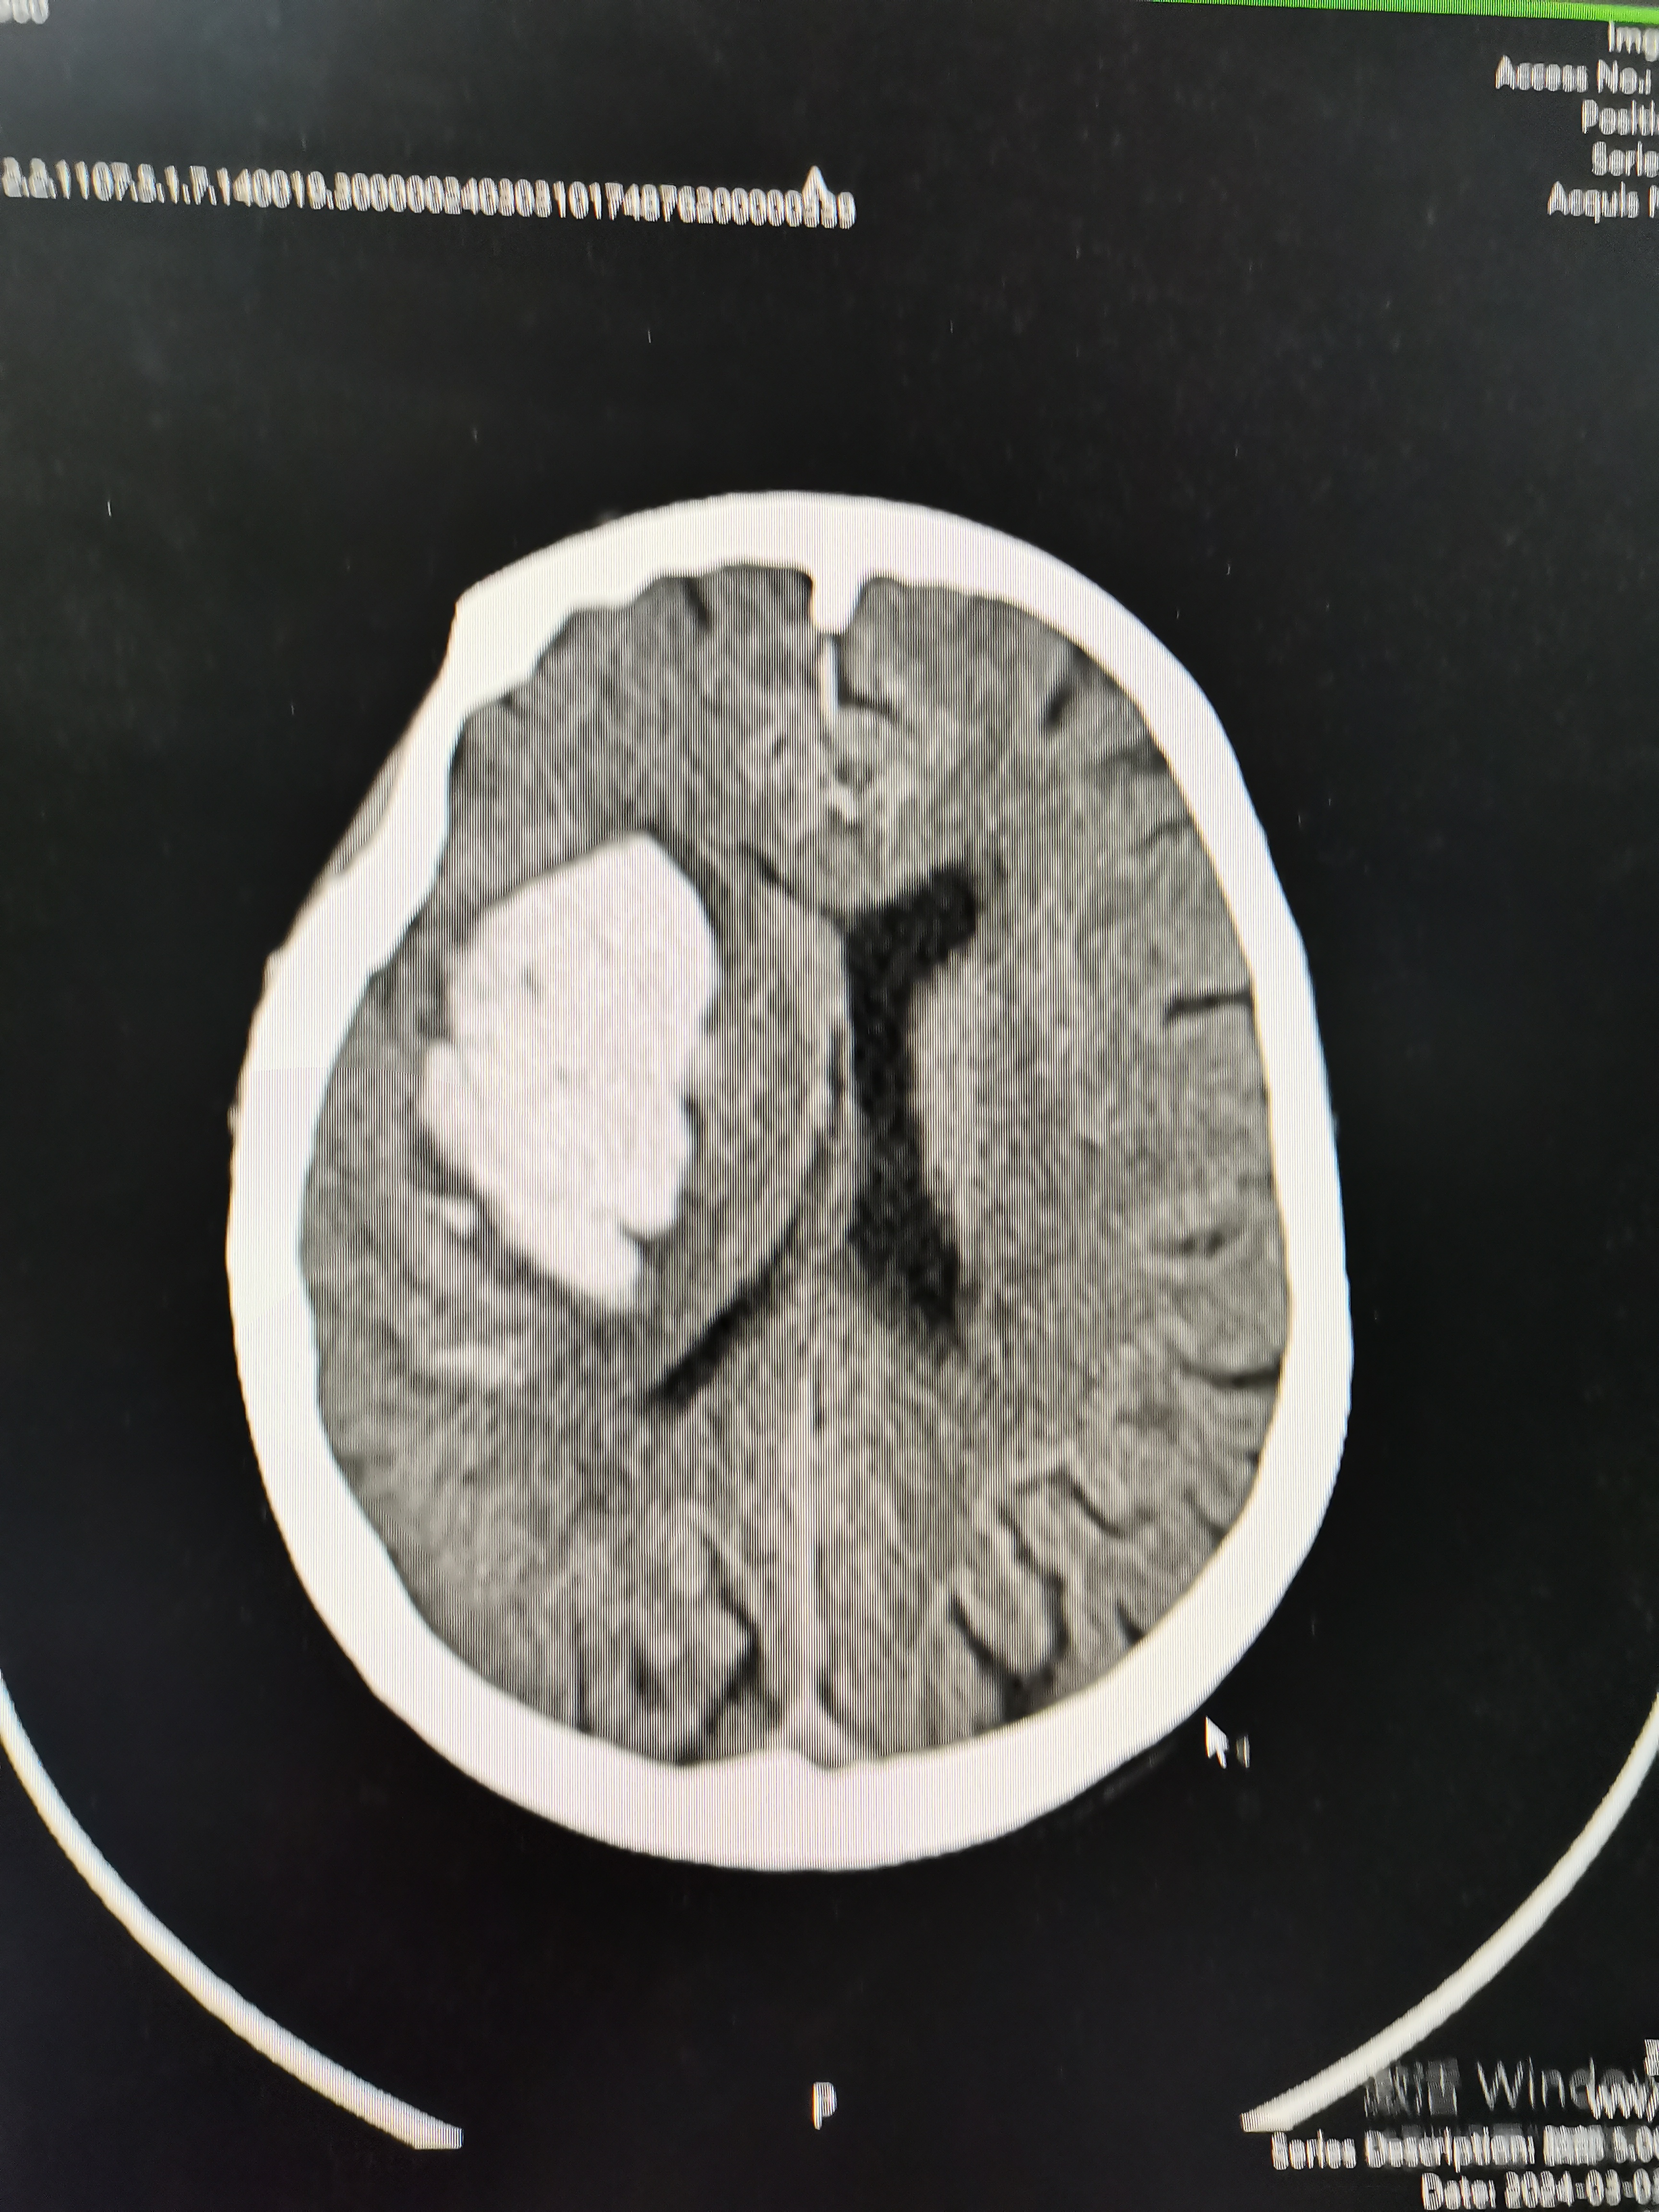

术后复查片子

患者术后恢复良好